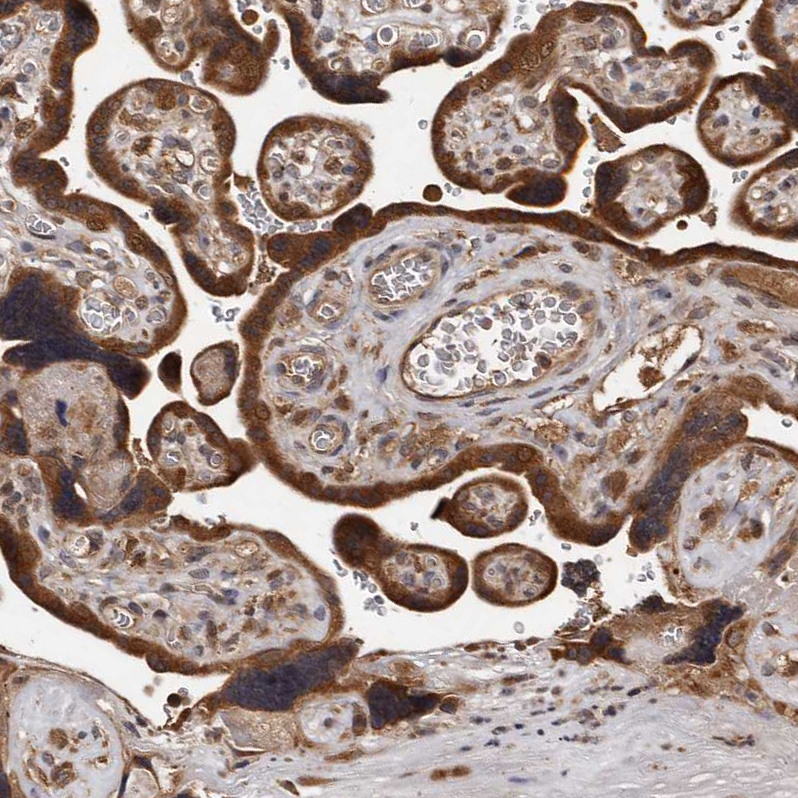

Immunohistochemical staining of human fallopian tube shows strong cytoplasmic positivity in glandular cells.